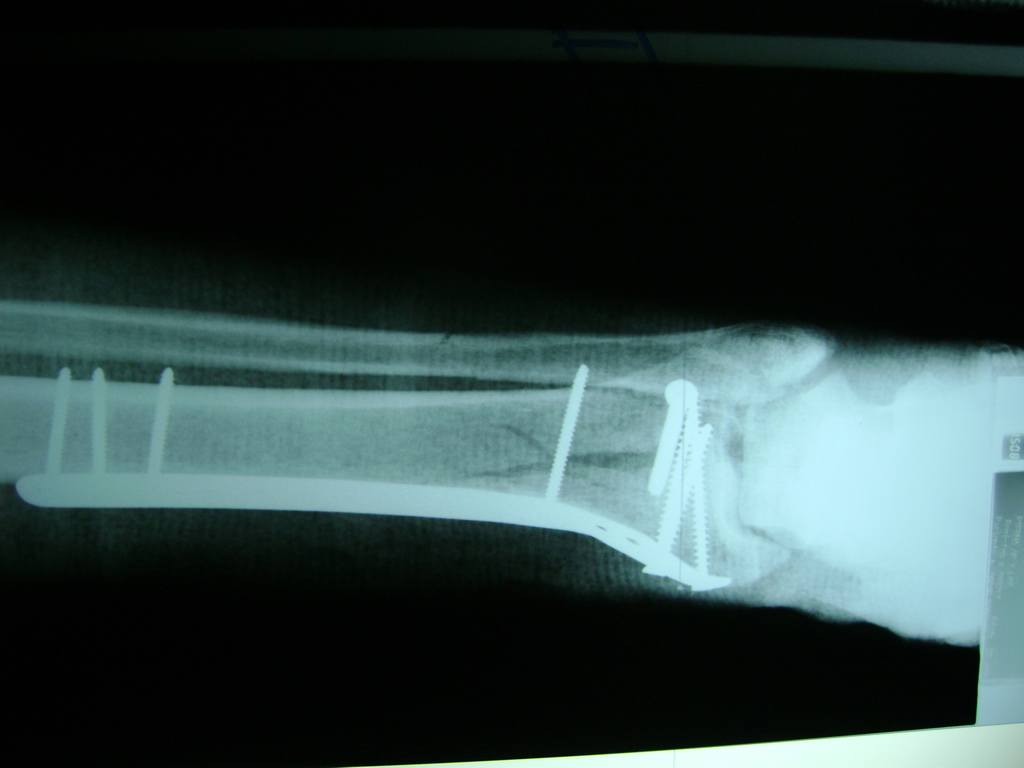

Cirugías de Codos - Perone y Tibia

Aunque cada uno de estos huesos puede fracturarse por separado, normalmente la rotura es una lesión que se produce de forma conjunta

La mayor parte de las roturas implican a la parte proximal del hueso (parte del hueso próximo a la rodilla) o a la parte distal (parte del hueso cerca del tobillo).

Debido a la fina cobertura de piel que recubre la tibia y el peroné, las fracturas generalmente son abiertas, es decir, el hueso roto rasga la piel, atravesándola. Las fracturas de tibia y peroné generalmente se producen por un fuerte impacto o torsión.